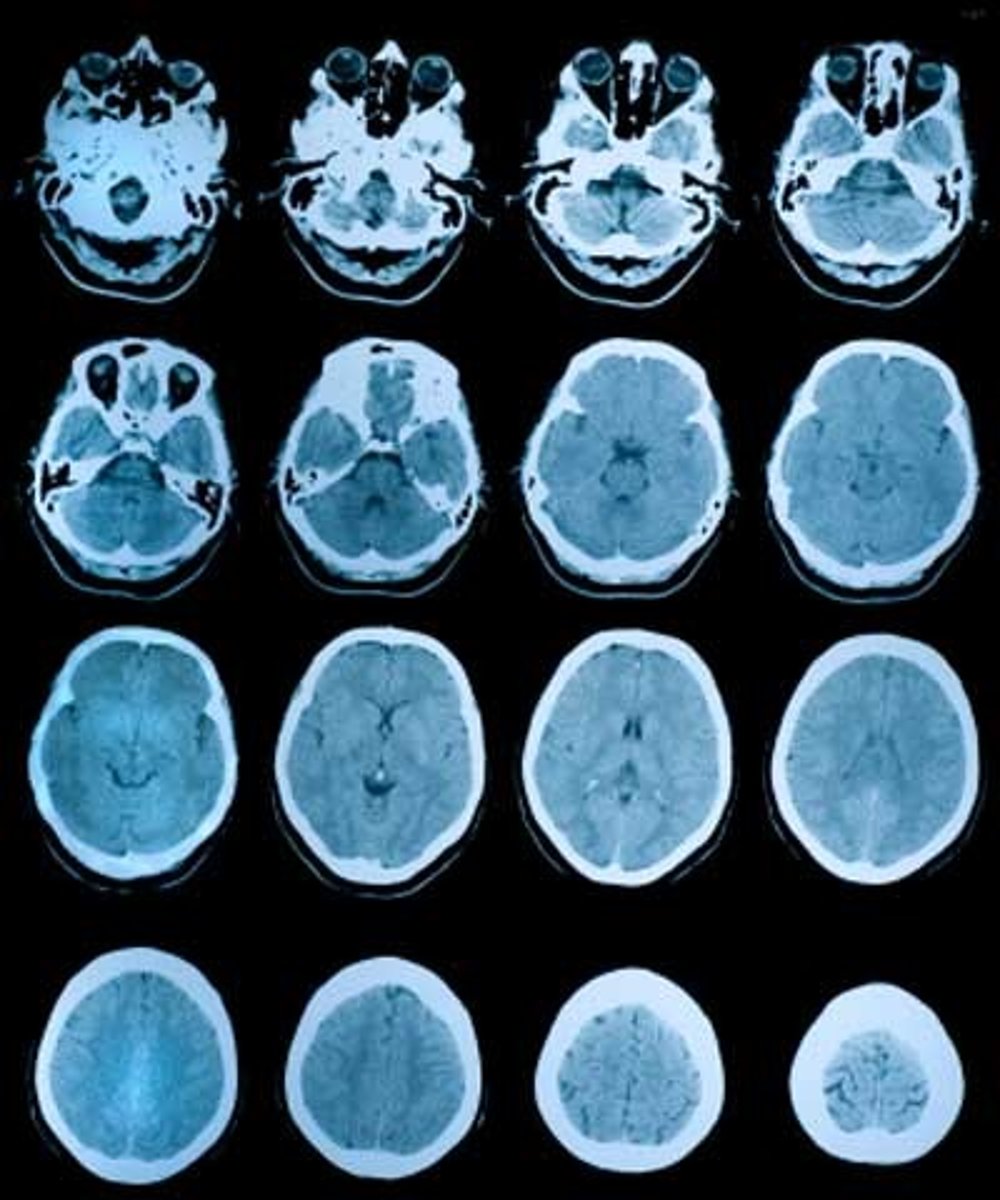

What does CAT scan stand for?

Computerized Axial Tomography

How do CAT scans work?

Uses multiple X-ray beams passed through the head, creating cross-sectional images of the brain. Sometimes dyes such as iodine are used

What images can CAT scans give us?

3D images or the slides can be looked at individually

What are CAT scans often used for?

To identify if brain damage is present

Describe the process of getting a CAT scan.

1. Remove all metal

(1.5. An injection of dye may be given)

2. Lie still on the scanning table for 20-30 mins

3. The table moves through the scanner and rotates around pts head